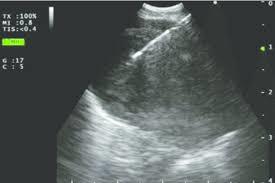

Both types of ultrasound contain a transducer head and a processor. The transducer helps to produce and receive the sound waves, while the processor combines the transmitted and reflected sound waves. The processor helps to create ultrasound images based on the absorption and scattering of the sound waves.

- It provides real-time images of the airways, lungs, lymph nodes, and blood vessels.

- Gives high-definition images that help the doctor to visualize the damaged areas in the lungs more easily.

- The bronchoscope is attached to a tiny camera and an ultrasound transducer at its end, which enables the doctor to view the airways, lymph nodes, blood vessels, and lungs on an ultrasound monitor.